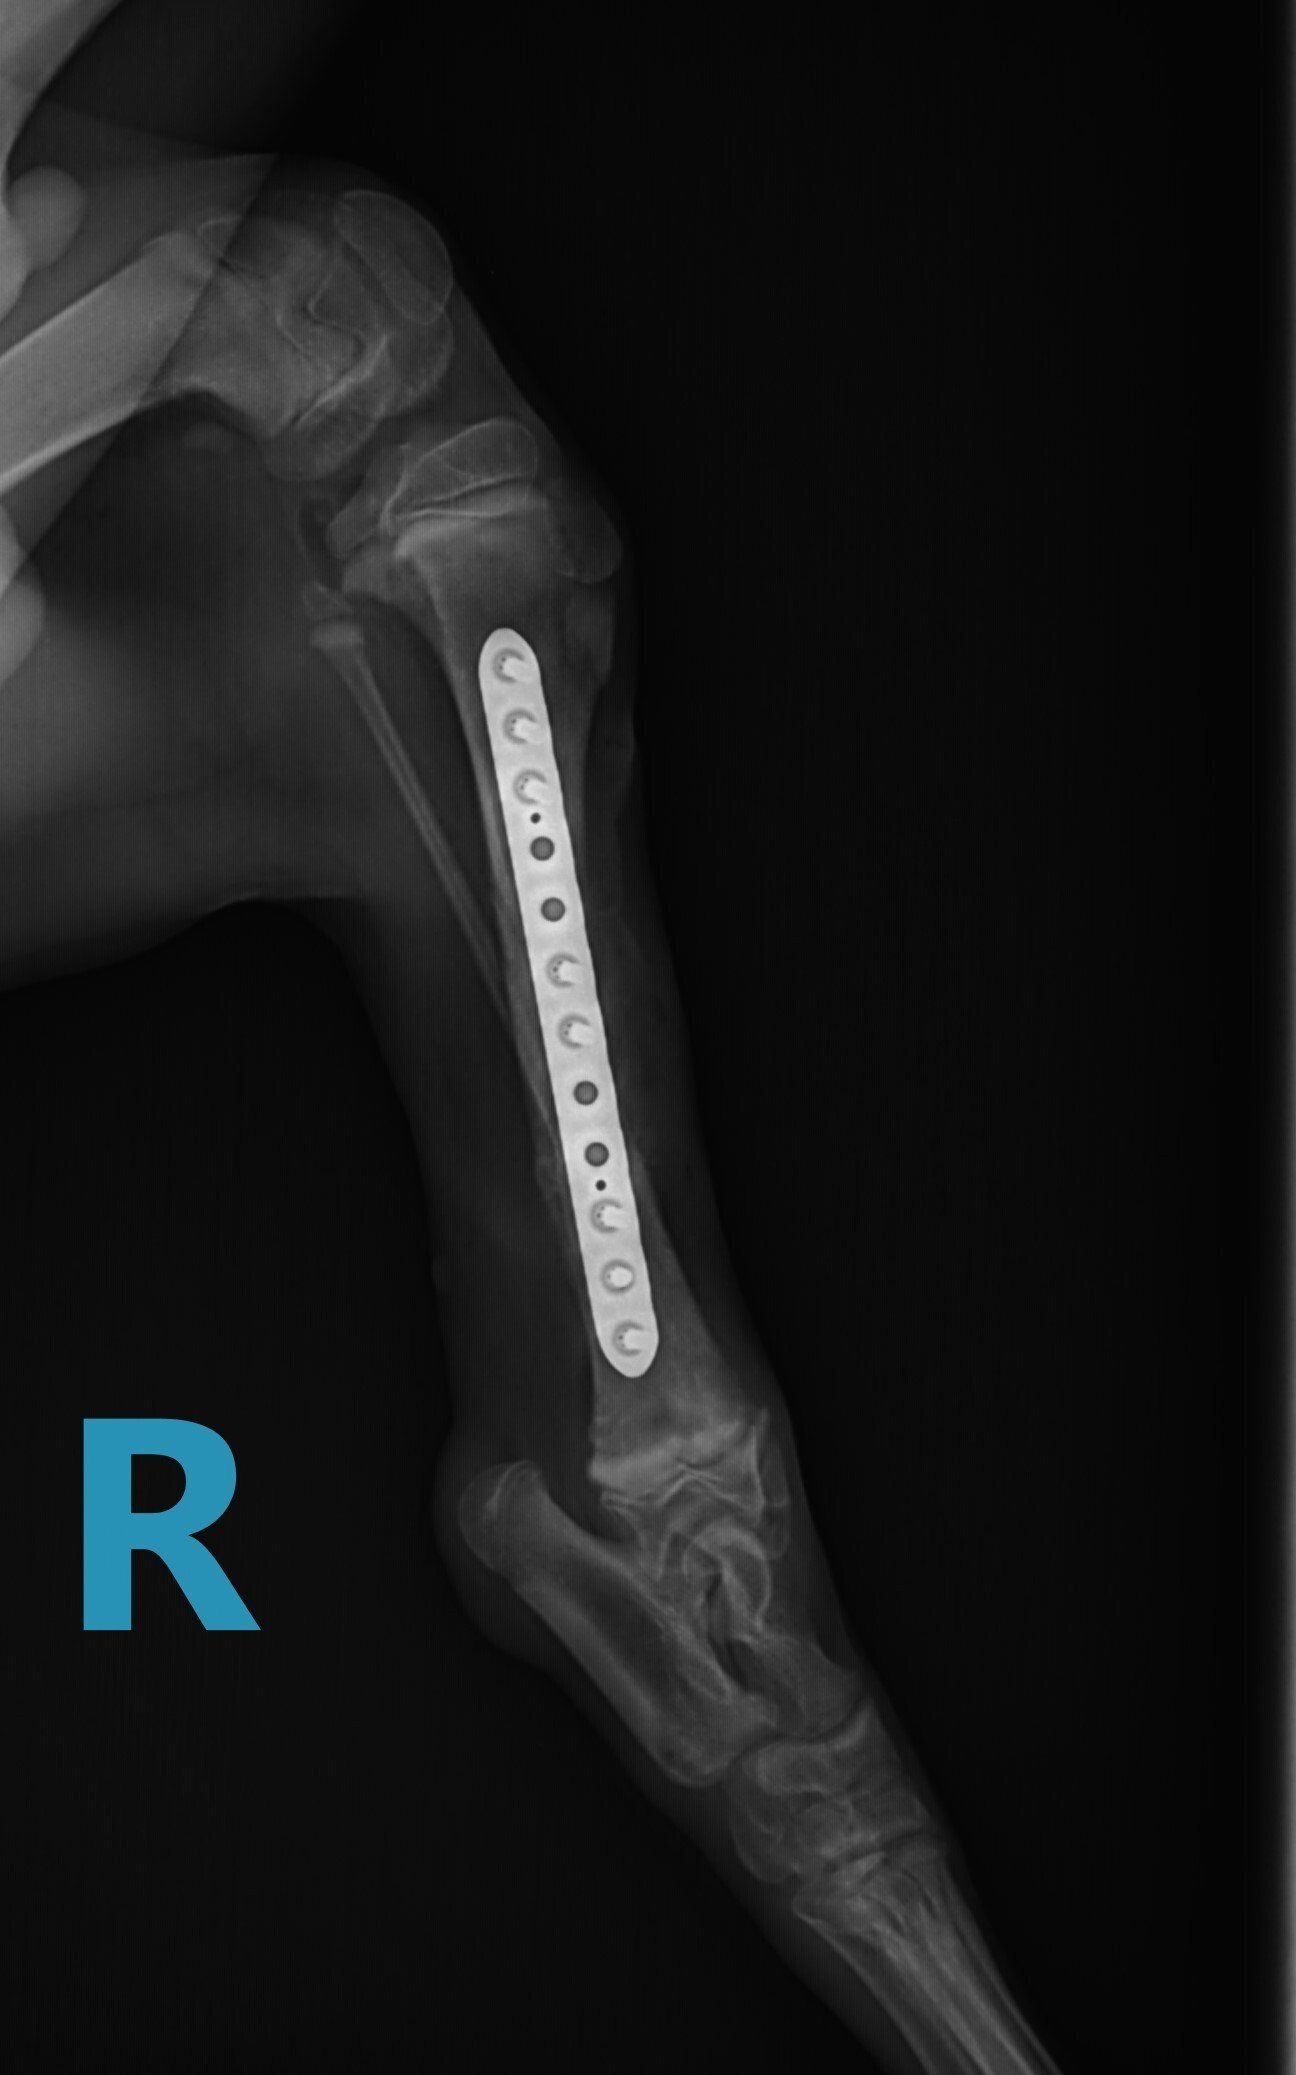

Leg fractures are one of the most common orthopedic problems presented at our clinic and usually result from a traumatic mishap. They can be treated in a variety of ways depending on the location and type of fracture. We can apply a cast to treat certain fractures; however, many fractures will require surgical intervention:

- “Pinning” stabilizes the fracture by inserting a long stainless steel rod into the middle of the bone across the fractured area.

- “Plating” involves attaching a flat stainless steel plate to the bone using screws on either side of the fracture.

Below are x-rays of just a few orthopedic surgeries before and after that Dr. Gose has performed.